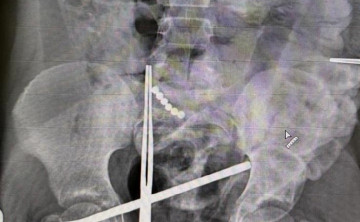

В Ростове мальчик проглотил 19 магнитных шариков и попал в реанимацию